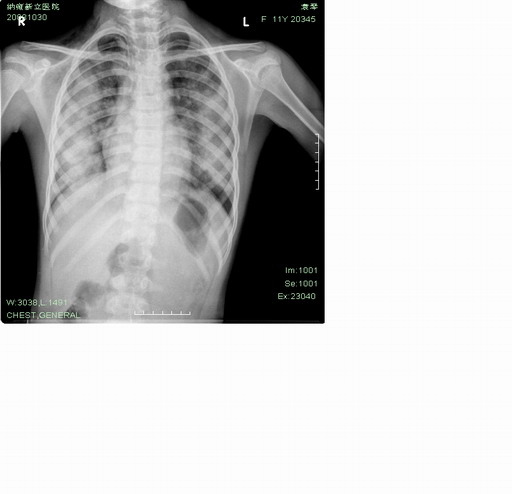

女性,11岁,咳嗽、咯血2小时入院,2年前有类似症状,但较轻。

两肺磨玻璃样改变,考虑出血性病变

两肺对称性大片状阴影,临床没有提示发热,血象也不清楚,但还是要考虑大叶性肺炎改变。

两肺对称性大片状阴影,两年前有相似症状,无相关影像资料,发病时间较短,暂考虑过敏性肺炎可能,建议ct检查,治疗后复查

两肺野中外带对称性大片状阴影,与胸廓平行,呈反肺水肿征,考虑慢性嗜酸细胞性肺炎。建议ct及生化检查,必要时肺泡液灌洗检查。

两肺以肺门为中心,大片棉团样高密度影,结合临床病史考虑肺出血,至于出血原因,还要进一步检查,尤其要密切关注泌尿系统,防止肺出血-肾炎综合征

鉴别:

1、感染,结核,临床中毒症状明显,普通感染引起大咯血的不多见

2、蛋白沉积症,主要症状为呼吸困难、咳嗽、低热、消瘦、低氧血症和杵状指等,与本例咯血的症状不符,没有看到特征性的“碎石路样”表现

两肺以肺门为中心,大片棉团样高密度影,结合临床病史考虑肺出血,至于出血原因,还要进一步检查,尤其要密切关注泌尿系统,2两年前有类似症状,高度怀疑肺出血-肾炎综合征